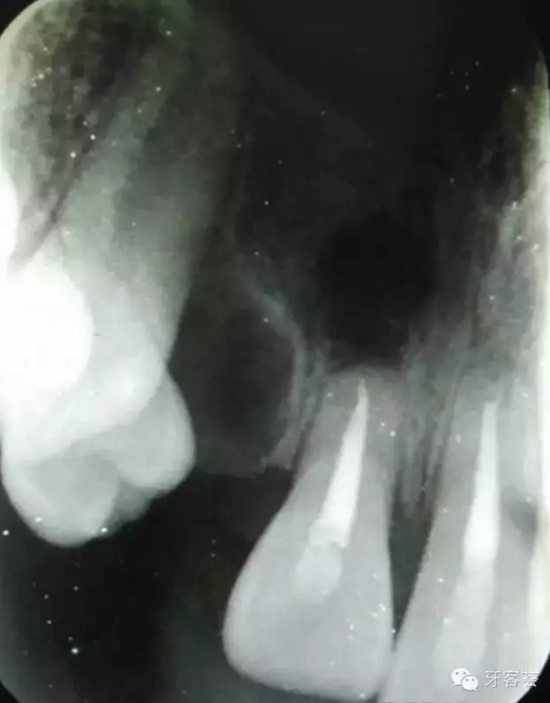

圖18:縫合術(shù)后的根尖片影像資料。12拔除,11根尖斷根完整取出。